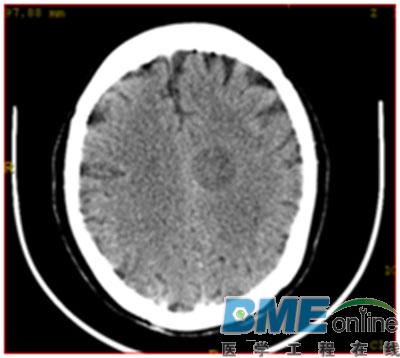

- GE CT图像满屏环形伪影,无报错故障维修

- 摘要:故障现象 一台GE PROSPEED AII双排螺旋CT机,扫描出来的图像满屏环形伪影,无报错提示。 故障分析及排除 分析故障可能原因有以下几种情况: 1、DAS电源电压异常; 2、CAM板故障; 3